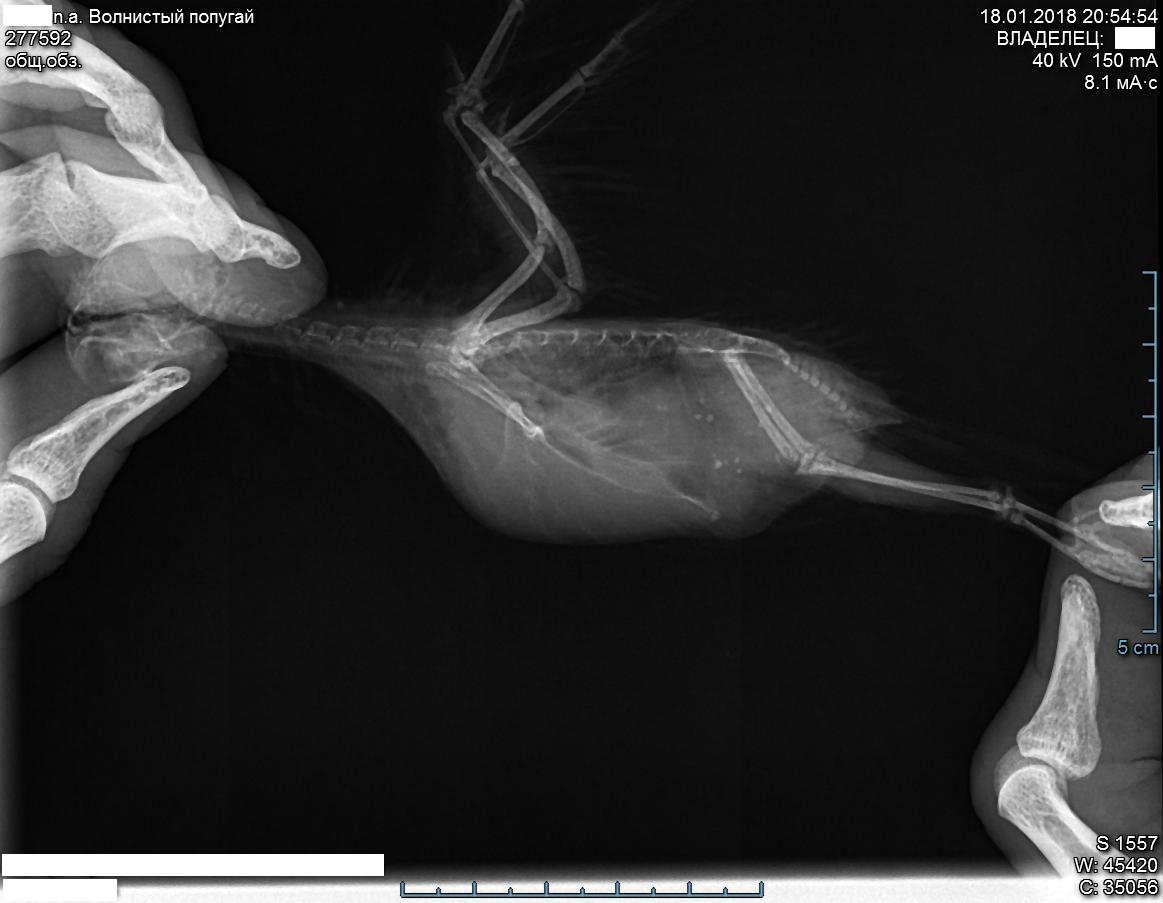

По рентгену. Кости у нас увеличены. Печень увеличена более, чем в 2 раза. Она "подвинула" (заняла часть места) воздушные мешки.

Такие размеры печени, насколько я запомнил, из-за гормонов (кажется так, но могу ошибаться - столько инфы за раз, мог не всё запомнить точно), выделяемых яичниками. Тут ещё один момент: у Лисы было активное спаривание с Шустриком в течение недели (каждый день) и ещё неделю (через день) где-то с середины ноября до начала декабря; а восковица у нас и сейчас довольно коричневая, хотя уже полтора месяца не спариваются). Наследственная эта патология или нет - пока неизвестно (в течение двух недель узнаем). Через две недели - повторный рентген.

Лечение назначено: гептрал, байтрил, локсиком, легалон 70, принудительное кормление безмолочными злаковыми кашами (вес сейчас 37г; 36г - нижняя граница, за которой на 100% начинается принудительное кормление, иначе мы умрём от истощения). Легалон - всегда, без отмены. Плюс придётся, скорее всего, супрелорин (имплант) для стерилизации, причём менять его придётся постоянно (по сути - как только Лисе станет плохеть, значит пора менять), т.к. точный срок его действия неизвестен (Алесандр говорил о 3-8 месяцах, но как будет в моём случае - неизвестно). Но и тут поджидает вероятно зло: если в яичниках находятся опухолевые клетки, то Лиса погибнет. Механическое удаление яичников в России пока не выполняют.